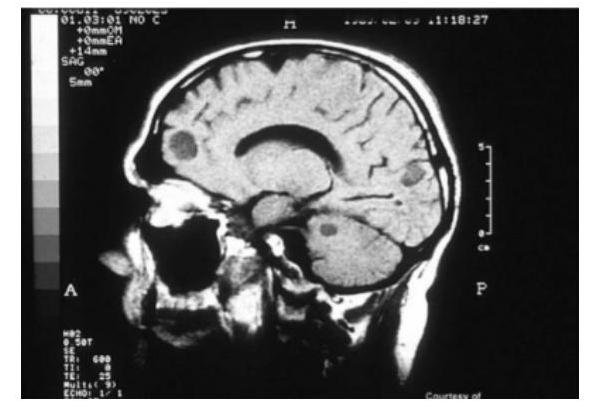

# **MICOSIS** DEFINICIÓN Las infecciones fúngicas pueden causar infección local o sistémica. En este apunte se revisarán las micosis sistémicas de mayor relevancia (las locales se abordan en Dermatología). Dentro de la presentación de las infecciones micóticas pueden presentarse: ## OPORTUNISTA Muchos hongos son **oportunistas** y no producen infecciones salvo que penetren en un individuo **inmunodeficiente**. Las causas del inmunocompromiso abarcan síndrome de inmunodeficiencia adquirida (**sida**), uremia, diabetes mellitus, linfoma, leucemia, otros cánceres hematológicos, quemaduras y tratamientos con corticoides, inmunosupresores o antimetabolitos. Los pacientes internados durante numerosos días en una **Unidad de Cuidados Intensivos (UCI)** pueden infectarse a través de procedimientos médicos, debido a enfermedades subyacentes y/o desnutrición. ## PRIMARIA Las micosis **primarias** suelen ser el resultado de la **inhalación de esporas**, que pueden causar una **neumonía localizada** como manifestación principal de la infección. En los pacientes inmunocompetentes, las micosis sistémicas típicas evolucionan crónicamente y las micosis diseminadas con neumonía y septicemia son infrecuentes; en caso de aparecer lesiones pulmonares, suelen avanzar con lentitud. En general, los pacientes tardan varios meses en consultar, lo que retrasa el diagnóstico. En estas micosis crónicas, los síntomas rara vez son intensos, pero los pacientes también pueden presentar fiebre, escalofríos, sudoración nocturna, anorexia, pérdida de peso, malestar general y depresión. Pueden comprometerse varios órganos, lo que provoca diversos síntomas y disfunciones. # **CANDIDIASIS** INVASORA ## DEFINICIÓN La **candidiasis** es una infección causada por especies de **Candida** (con mayor frecuencia **C. albicans**), que se manifiesta con lesiones mucocutáneas, fungemia y, en ocasiones, infecciones localizadas en múltiples sitios. ## ETIOLOGÍA Las especies de **Candida** son microorganismos comensales que habitan en el tubo digestivo y a veces en la piel. A diferencia de otras micosis sistémicas, la **candidiasis** se debe a una infección por microorganismos **endógenos**. La mayoría de las infecciones son causadas por **C. albicans**, aunque la **C. glabrata** (antes denominada Torulopsis glabrata) y otras especies no-albicans son responsables del desarrollo de fungemia, infecciones urinarias y, en ocasiones, otras enfermedades localizadas cada vez con mayor frecuencia. ## CLÍNICA ## **CANDIDIASIS** ORAL Se manifiesta como un exudado blanco que cubre una superficie mucosa carnosa, de color rojo y en carne viva de la mucosa labial. ## **CANDIDIASIS** ESOFÁGICA La **candidiasis** del esófago es una infección **oportunista** que define el desarrollo de **SIDA**. Aunque la candidiasis mucocutánea se detecta con asiduidad en pacientes infectados por **HIV**, la diseminación hematógena es inusual a menos que haya otros factores de riesgo específicos. ## **CANDIDIASIS** DISEMINADA Los pacientes **neutropénicos** (p. ej., los que reciben quimioterapia debido a cáncer) presentan un riesgo elevado de desarrollar **candidiasis generalizada**, que amenaza la  vida del paciente. Un paciente **no neutropénico** puede desarrollar **candidemia** durante una hospitalización prolongada. Esta infección hematógena suele estar relacionada con uno o varios de los siguientes elementos: - Catéteres venosos centrales - Cirugía mayor - Terapia con antibióticos de amplio espectro - Hiperalimentación intravenosa - Las **vías intravenosas** y el **tubo digestivo** suelen ser las puertas de entrada de la infección. # **CANDIDEMIA** La **candidemia** a menudo prolonga la internación y aumenta la tasa de mortalidad debido al desarrollo de enfermedades concurrentes. La **candidemia** puede ocurrir con otras formas de **candidiasis invasora**, como endocarditis o meningitis, además del compromiso localizado de la piel, los tejidos subcutáneos, los huesos, las articulaciones, el hígado, el bazo, los riñones, los ojos y otros tejidos. Todas las formas de **candidiasis generalizada** deben considerarse graves, progresivas y potencialmente fatales. ## DIAGNÓSTICO ## CULTIVO Las especies de **Candida** son comensales. Su cultivo del esputo, la boca, la vagina, la orina, las heces o la piel no indica necesariamente una infección invasora y progresiva. ## EXAMEN HISTOLÓGICO Debe identificarse una lesión clínica característica, con evidencias histológicas de invasión tisular (p. ej., levaduras, seudohifas o hifas en las muestras de tejido) y deben excluirse otras causas. ## **BETA GLUCANO SÉRICO**  Es a menudo positivo en pacientes con **candidiasis invasiva**; por el contrario, un resultado negativo indica baja probabilidad de infección sistémica. ## TRATAMIENTO | CANDIDIASIS ESOFÁGICA | CANDIDIASIS INVASIVA | | :-- | :-- | | **1RA ELECCIÓN: FLUCONAZOL** | **1ra elección: CASPOFUNGINA** | | 2da elección: Itraconazol | **2da elección: MICAFUNGINA** | | | **3ra elección: ANIDULAFUNGINA** | | ALTERNATIVAS (INEFICAS / INFECCIÓN GRAVE) | | | - Voriconazol | | | - Posaconazol | | | - Equinocandinas | | # **CRIPTOCOCOSIS** La **criptococosis** es una infección pulmonar o generalizada que se adquiere a través de la inhalación de tierra contaminada con las levaduras encapsuladas **Cryptococcus neoformans** o **C. gattii**. Puede presentar infección del **Sistema Nervioso Central (Meningitis Criptocócica)**. ## ETIOLOGÍA El **Cryptococcus neoformans** es un hongo levaduriforme que se aísla del suelo (deyecciones de palomas). **C. gattii** se asocia principalmente con los árboles, especialmente el eucalipto (no se asocia a las aves). - Se adquiere por **inhalación** de las levaduras. - Se disemina vía **Hematógena** al sistema nervioso (**FOCOS EN ÁREAS PERIVASCULARES DE LA CORTEZA**). ## FACTORES DE **RIESGO** - **SIDA** (La criptococosis es una infección oportunista determinante de sida, típicamente asociada con recuentos de CD4 < 100/$\mu$L). - Linfoma de Hodgkin - Sarcoidosis - Trasplante de órgano sólido - Terapia con esteroide prolongada ## CLÍNICA ## **MENINGOENCEFALITIS** (**SNC**) Especialmente en inmunodeprimidos por **SIDA** y Tratamiento prolongado con **corticoides**. - Dado que la inflamación no es extensa, la fiebre suele ser baja o estar ausente y los signos meníngeos son habituales. - En los pacientes con **sida**, la meningitis criptocócica puede causar pocos o ningún síntoma, pero con frecuencia genera cefalea y a veces un estado mental alterado de progresión lenta.  - Puede presentarse en **pulmones** (tos y síntomas respiratorios inespecíficos) y en **Piel** (lesiones pustulosas, papulares o ulceradas). ## DIAGNÓSTICO # **GOLD STANDARD: CULTIVO** Se puede encontrar por orina o en sangre. ## **1ra elección: TINCIÓN DE TINTA CHINA LCR** - Tiene mayor sensibilidad en los que están en fase de **SIDA**. ## DETECCIÓN **ANTÍGENO CAPSULAR** - Se aglutina con látex en el **LCR**. ## TRATAMIENTO ## **1ra elección: ANFOTERICINA B** **CONSOLIDACIÓN** - **FLUCONAZOL** 400 mg diarios durante 8 semanas. **MANTENIMIENTO** - **FLUCONAZOL** 200 mg diarios durante 6 - 12 meses. ## **ESPOROTRICOSIS** - El hábitat natural de este hongo es la **vegetación viva o muerta**. - Traumatismo típicamente por **pinchazo con un rosal**. ## CLÍNICA 1. Produce **úlcera que no cura**. 2. Afecta a **vasos linfáticos** y **ganglios** de territorio de drenaje. ## DIAGNÓSTICO  - Cultivo - pus, líquido articular - **Agar SABOURAUD a 30$^{\circ}$C**. - Forma colonias negras de hifas oscuras. - Biopsia cutánea (poco rentable). ## TRATAMIENTO 1. **Yoduro Potásico** 2. **ITRACONAZOL** 3. **ANFOTERICINA B**